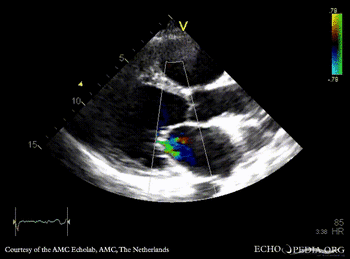

A4CH A4CH with Color Doppler: severe mitral valve regurgitation